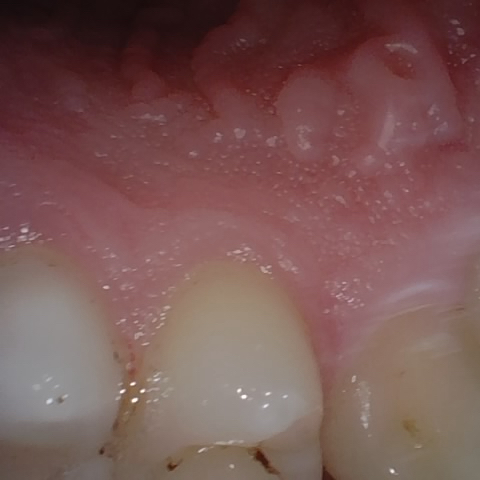

Annotated as "Good"

Original Image Rendering Image